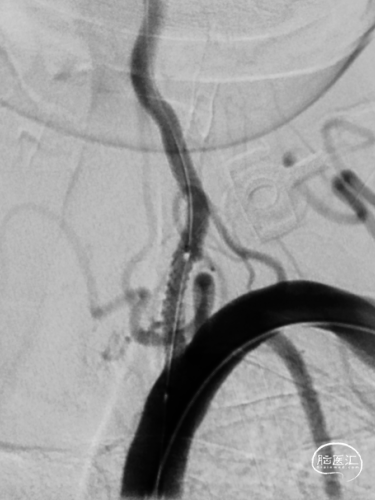

沿微导丝送入3.0mm*16mm Bridge椎动脉雷帕霉素靶向洗脱支架到达目标位置。经手推造影确认定位后,缓慢加压释放支架。